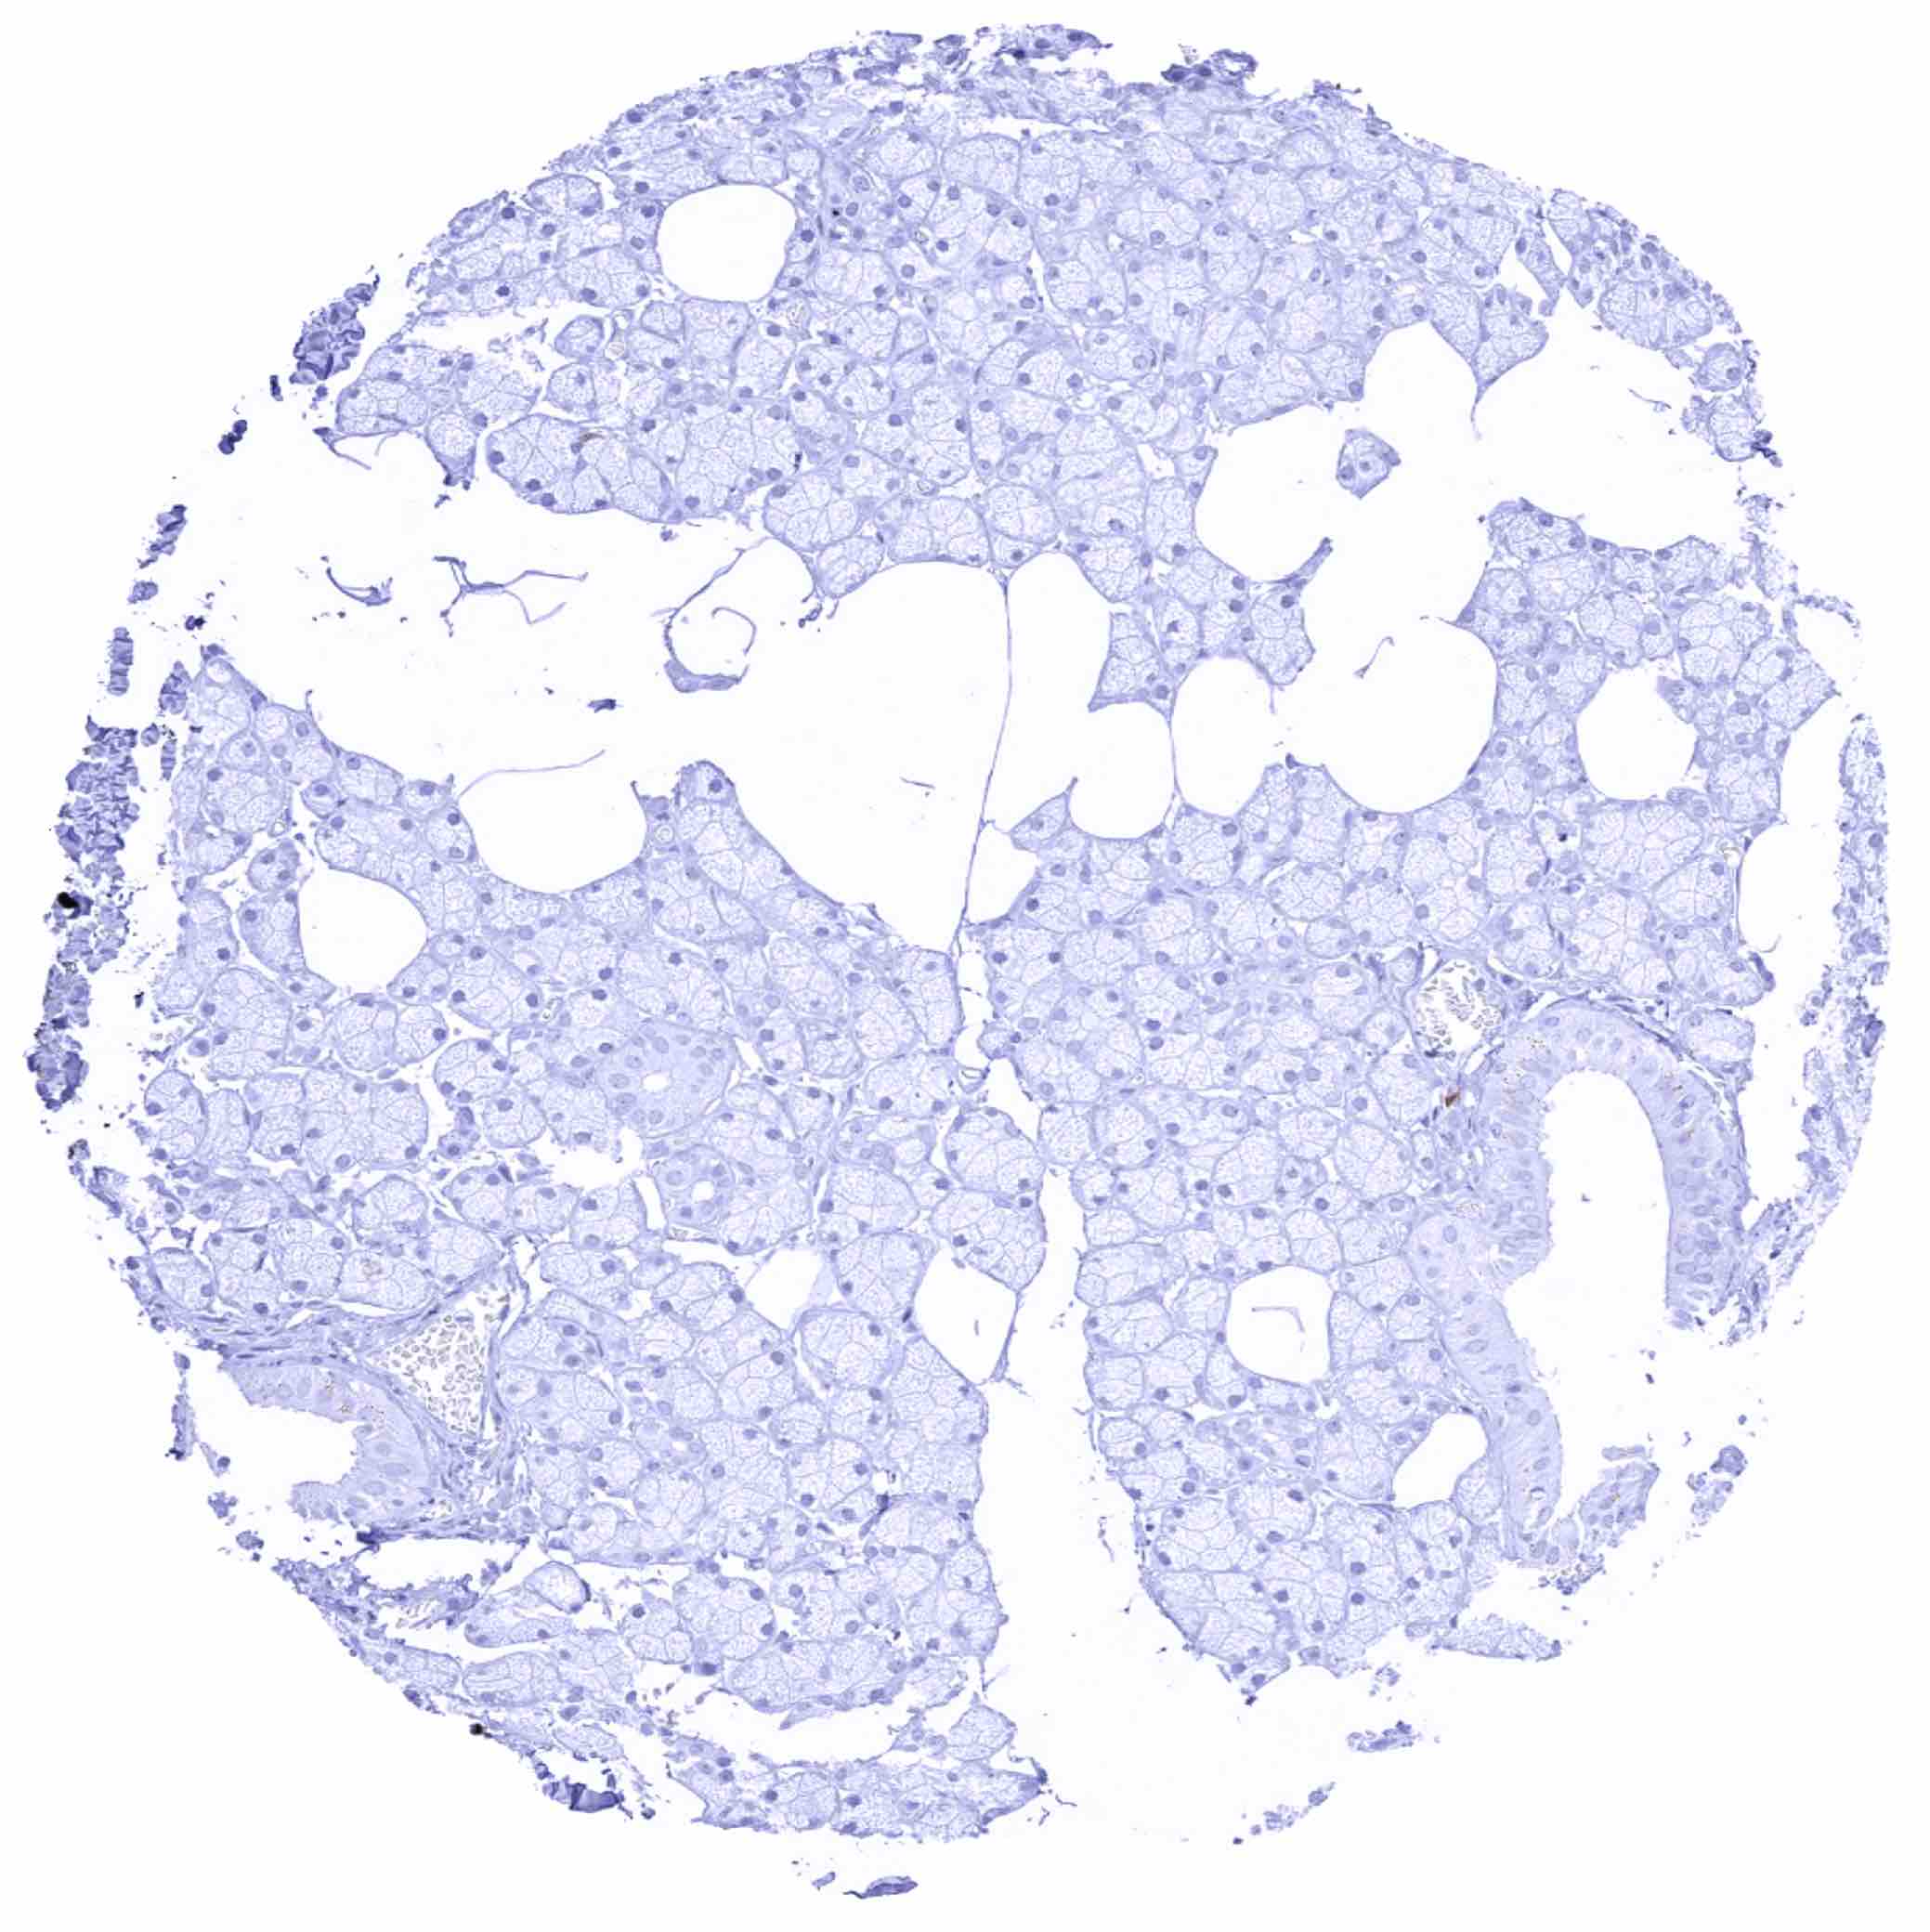

Thyroid gland